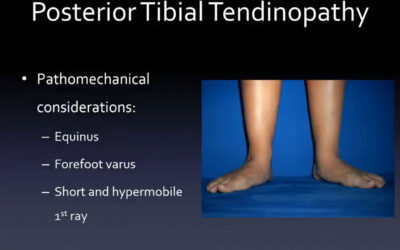

lerEXPO Conversations*: Bracing Posterior Tibial Tendon Dysfunction Long Term

Posterior Tibial Tendon Dysfunction (PTTD) is a pervasive condition impacting the foot and ankle, representing a significant challenge in long-term management for both the patient and the healthcare team. This dysfunction occurs when the posterior tibial tendon, a vital structural support for the arch that enables efficient foot function, becomes injured or degraded, either through…

By Roger Marzano, CPO, CPed